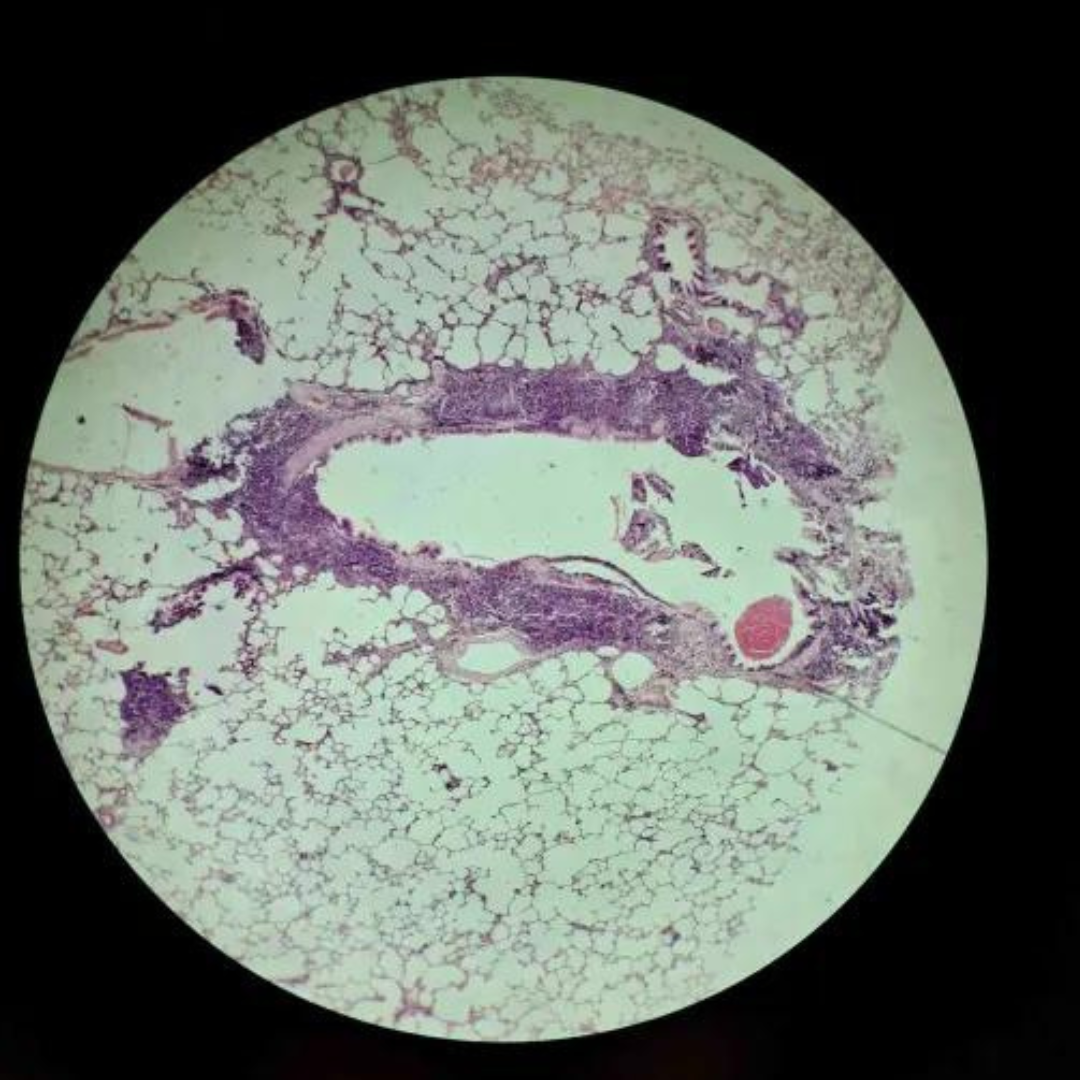

Lungs

Lungs

Lungs

Lungs

Lungs

Lungs

Lungs